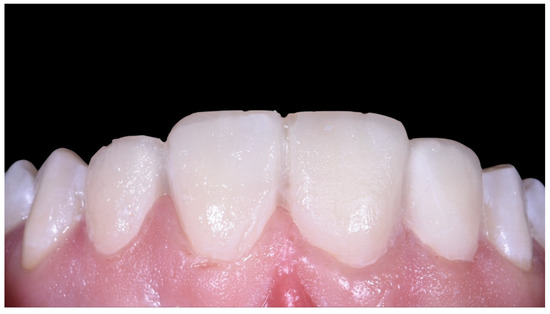

Case Report